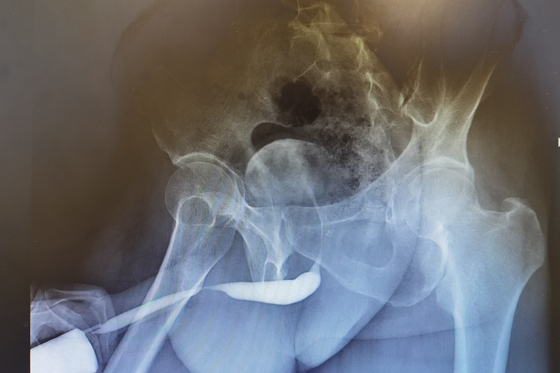

尿道造影显示前尿道长段狭窄

经过多方打听,他找到湘雅常德医院顿金庚教授,希望得到有效救治。经进一步检查发现,患者成先生距离尿道外口6㎝处有4公分长的前尿道狭窄,这是导致小便困难的罪魁祸首。